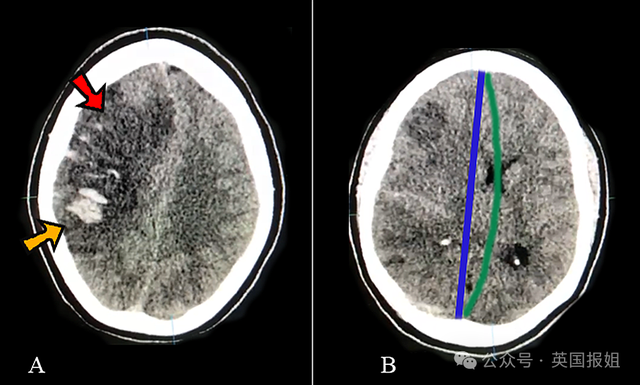

《世界临床病例杂志》在2022年分享过类似的病例,患者是一名29岁的孕妇,因剧烈恶心呕吐1周,最开始被诊断为妊娠剧吐,但后来病情恶化,最严重的时候已经出现急性左侧偏瘫。

好在进行及时检查和血栓切除术后,患者顺利康复,3周后能独立生活,随访3个月症状无复发。

(示意图)

案例还提到,由于CVT发病率低且临床表现多样,临床诊断具有挑战性,很容易把初期症状诊断为别的因素。